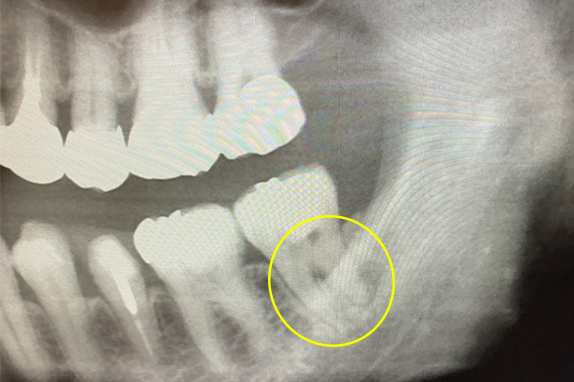

CASE 08 マイクロエンド(精密根管治療)+静脈内鎮静法(リラックス外来)

-

- 主訴

- 歯ぐきがよく腫れる(50代女性)

-

- 回数期間

- 1回

-

- 治療法

- マイクロエンド(精密根管治療)、静脈内鎮静法(リラックス外来)

-

- 治療費用

- 25万円(税抜)

歯ぐきがよく腫れる主訴で来院。患者様の要望で静脈内鎮静法(リラックス外来)を施しマイクロエンド(精密根管治療)で改善したケースです。

<リスク・副作用>

治療後は痛み、腫れ、痺れなどの副作用が生じる場合があります。症状が再発する可能性があります。